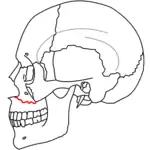

Le Fort III fractures

At the beginning of the 20th century, René Le Fort mapped typical locations for facial fractures; these are now known as Le Fort I, II, and III fractures (right).[7] Le Fort I fractures, also called Guérin or horizontal maxillary fractures,[14] involve the maxilla, separating it from the palate.[15] Le Fort II fractures, also called pyramidal fractures of the maxilla,[16] cross the nasal bones and the orbital rim.[15] Le Fort III fractures, also called craniofacial disjunction and transverse facial fractures,[17] cross the front of the maxilla and involve the lacrimal bone, the lamina papyracea, and the orbital floor, and often involve the ethmoid bone,[15] are the most serious.[18] Le Fort fractures, which account for 10–20% of facial fractures, are often associated with other serious injuries.[15] Le Fort made his classifications based on work with cadaver skulls, and the classification system has been criticized as imprecise and simplistic since most midface fractures involve a combination of Le Fort fractures.[15] Although most facial fractures do not follow the patterns described by Le Fort precisely, the system is still used to categorize injuries.[5]